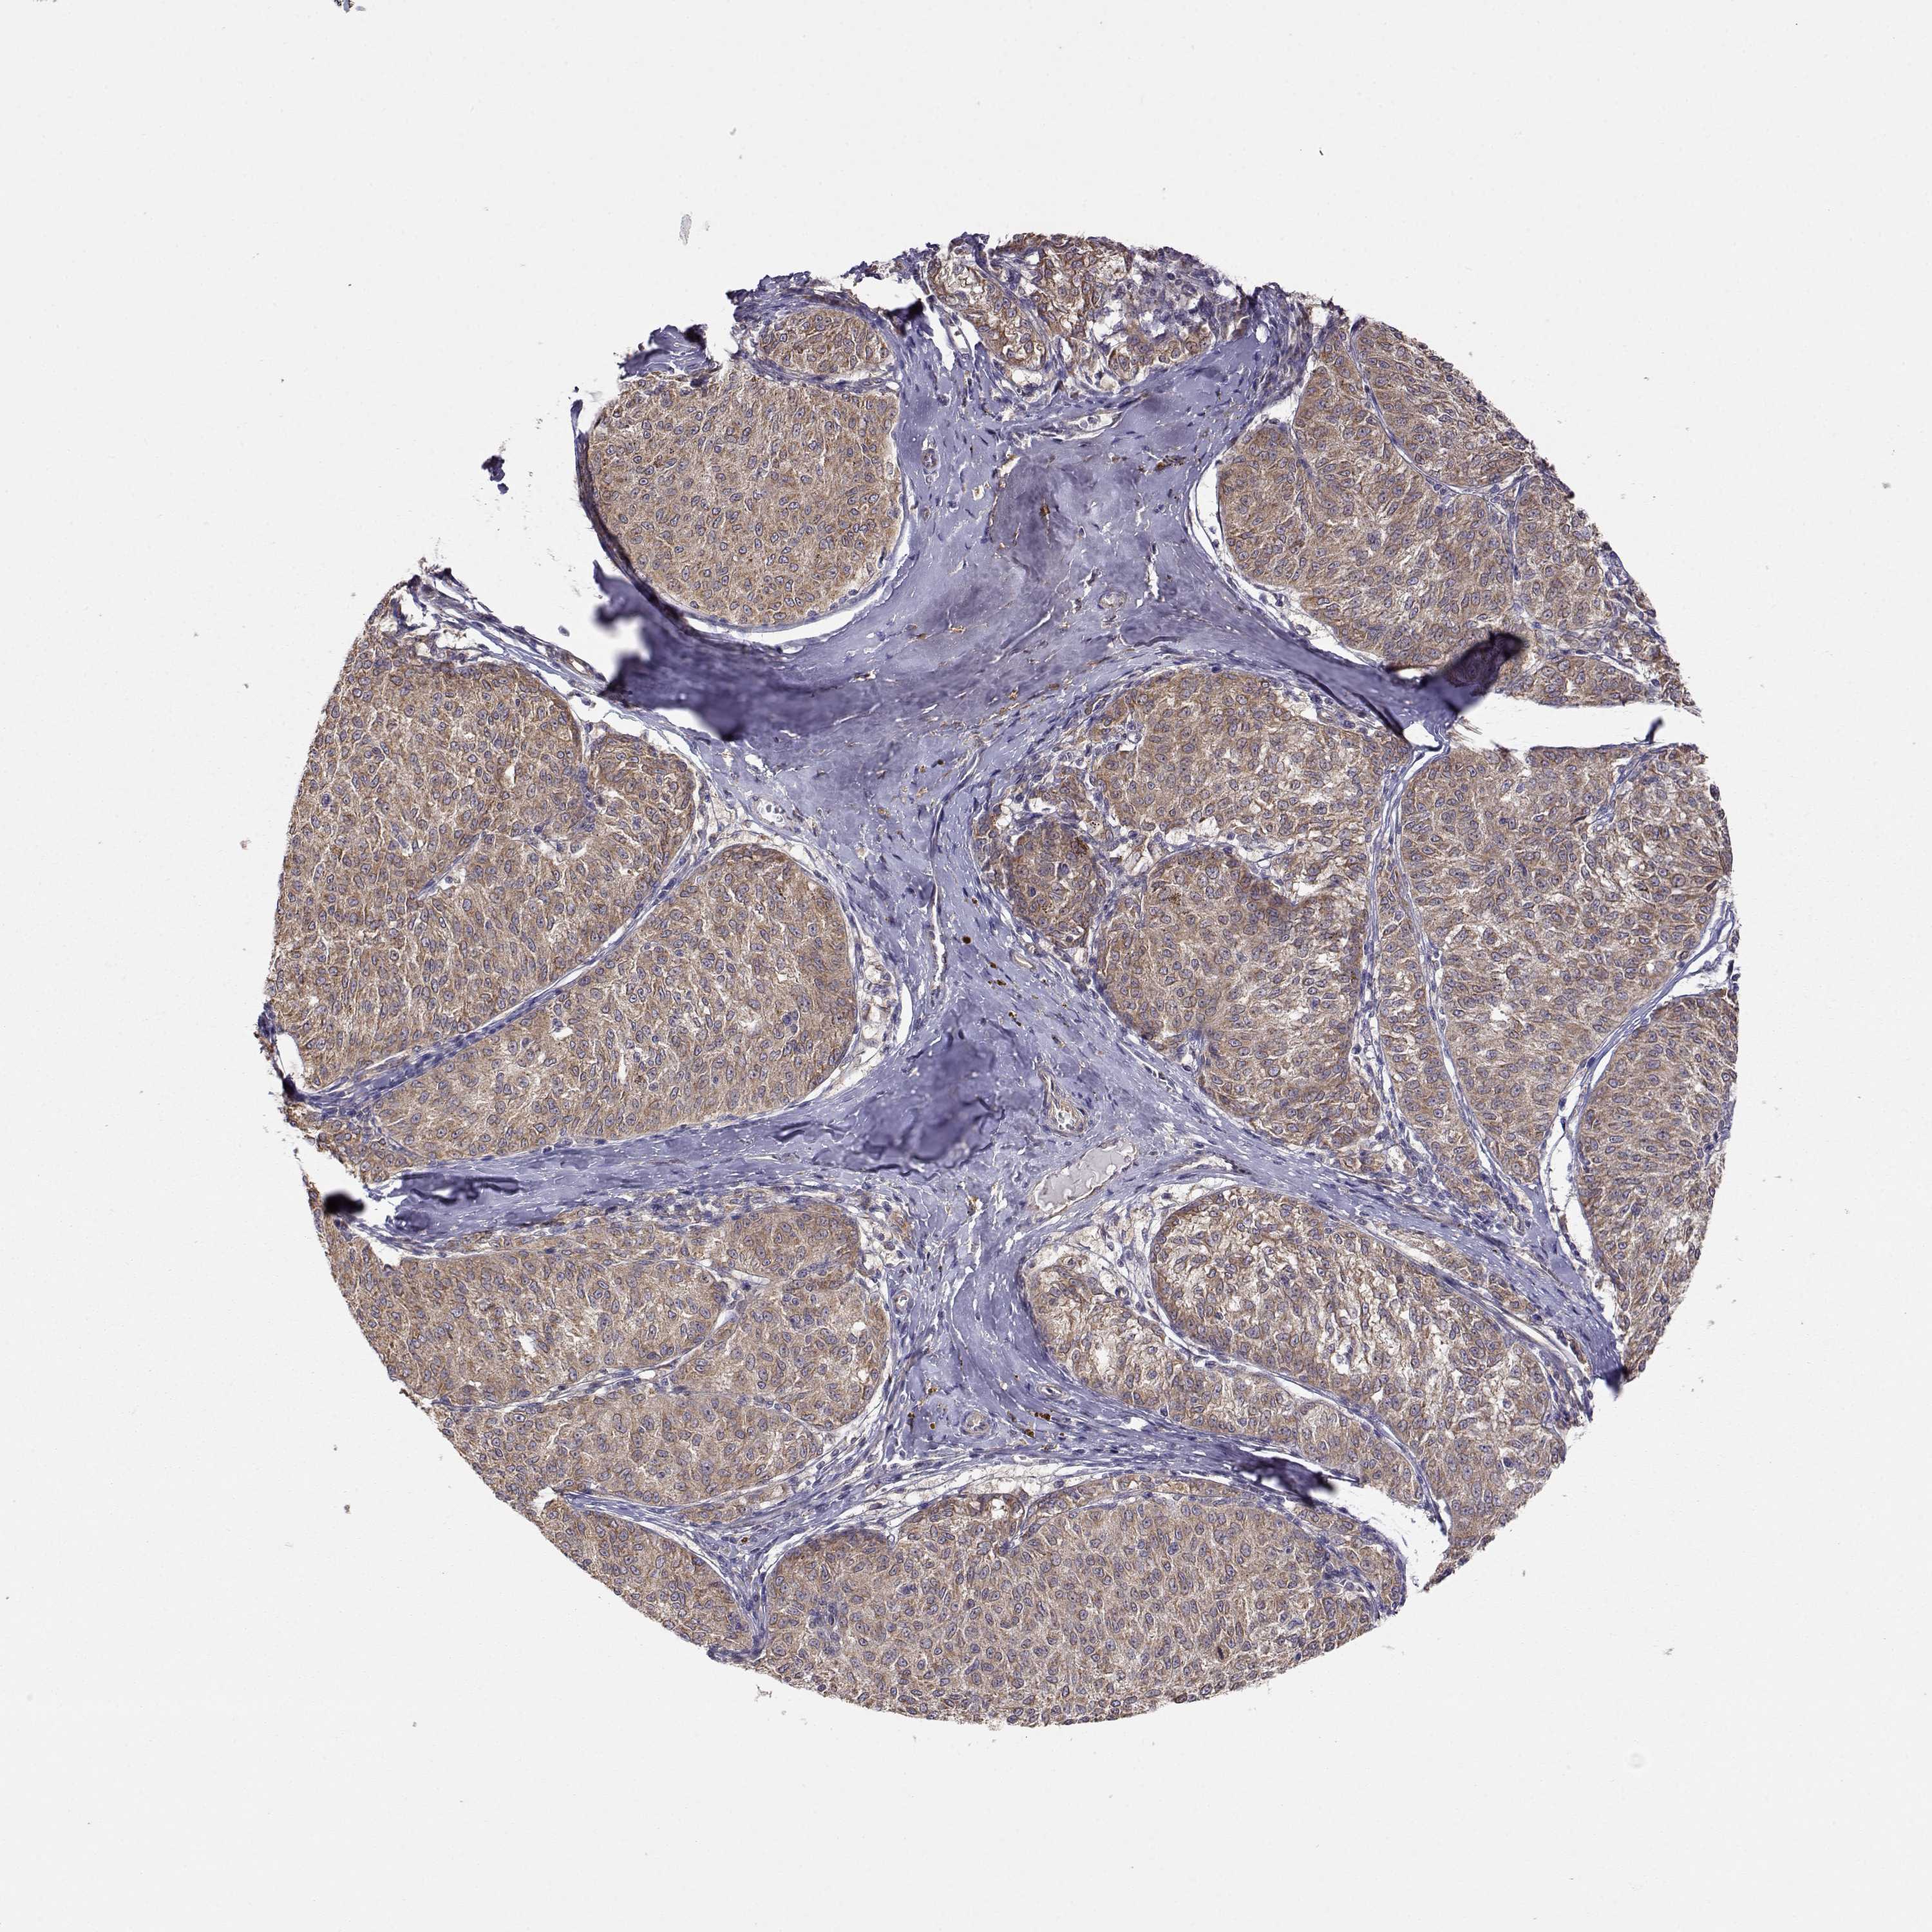

MELANOMA - Protein expressioni

A mouse-over function shows sample information and annotation data. Click on an image to view it in a full screen mode. Samples can be filtered based on level of antibody staining by selecting one or several of the following categories: high, medium, low and not detected. The assay and annotation is described here.

Note that samples used for immunohistochemistry by the Human Protein Atlas do not correspond to samples in the TCGA dataset.

Antibody stainingi

Antibody staining in the annotated cell types in the current human tissue is reported as not detected, low, medium, or high, based on conventional immunohistochemistry profiling in selected tissues. This score is based on the combination of the staining intensity and fraction of stained cells.

Each image is clickable and will lead to virtual microscopy that enables deeper exploration of all samples and also displays staining intensity scores, fraction scores and subcellular localization as well as patient and tissue information for each sample.

Antibody HPA073653

Staining

High

Medium

Low

Not detected

Intensity

Strong

Moderate

Weak

Negative

Quantity

>75%

75%-25%

<25%

None

Location

Nuclear

Cytoplasmic/membranous

Cytoplasmic/membranous,nuclear

Malignant melanoma, NOS

Malignant melanoma, Metastatic site